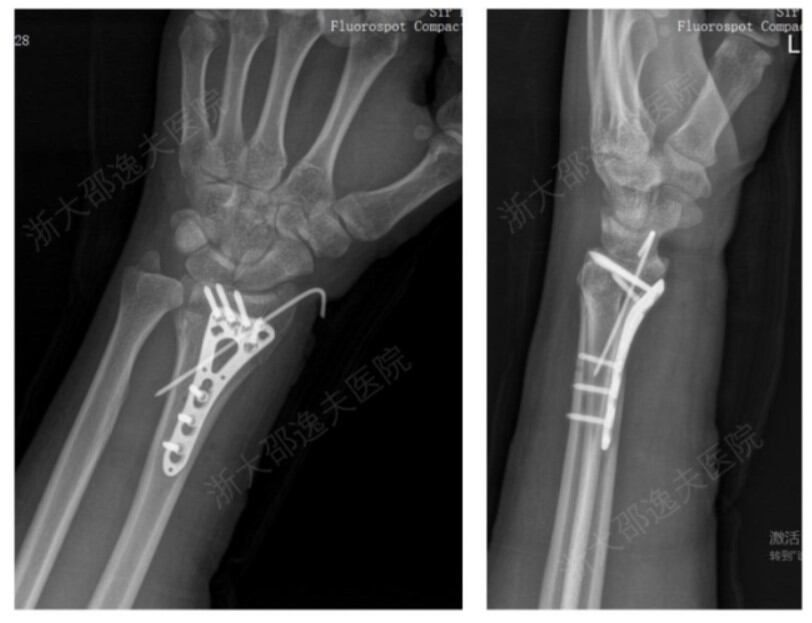

実際、手首の粉砕骨折で「骨02」治療を受けた患者は、たった2~3cmの切開を通して注入された接着剤により、たった3分で折れた骨を固定することができた。従来の治療法では、大きな切開を通じて鉄板とネジを挿入し、その後1年後に除去手術を受ける必要があったが、3ヶ月の追跡観察の結果、この患者の骨折は合併症なく良好に治癒し、手首の機能も完全に回復した。